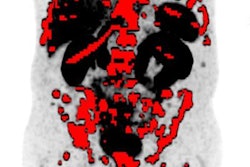

A 75-year-old with elevated PSA (5.2 ng/mL) and an unclear, not well-demarcated lesion on the right peripheral base of the prostate on multiparametric MRI. PSMA PET/MRI showed increased activity in the suspicious lesion. The fused PSMA PET/MRI DICOM dataset was imported to MedCom's BiopSee system, and targeted biopsy was performed. Histopathology confirmed aggressive prostate cancer (Gleason score 4+4). Images courtesy of Dr. Irene Burger.Ga-68 PSMA-11 PET provided positive prostate cancer results in 16 cases (64%) with a median SUVmax of 7.8 (range, 5.2-19.3). One significant cancer (4%) was missed by Ga-68 PSMA-11 PET, and there was one false positive (4%).